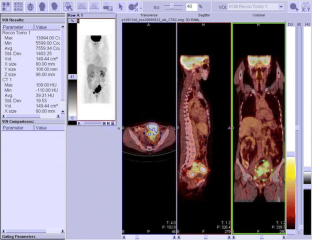

Fig. 1

Fig. 2

Fig. 3